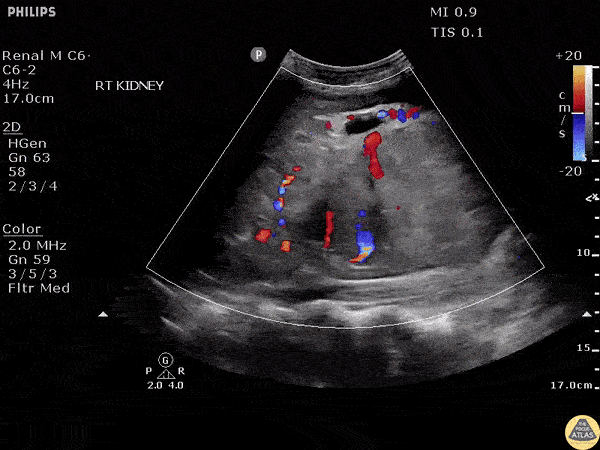

Renal parenchyma showed a dysmorphic appearance with the presence of mild ascites in this patient with flank pain and hematuria. Patient was later diagnosed with renal cell carcinoma. Image courtesy of Robert Jones DO, FACEP @RJonesSonoEM Director, Emergency Ultrasound; MetroHealth Medical Center; Professor, Case Western Reserve Medical School, Cleveland, OH View his original post here